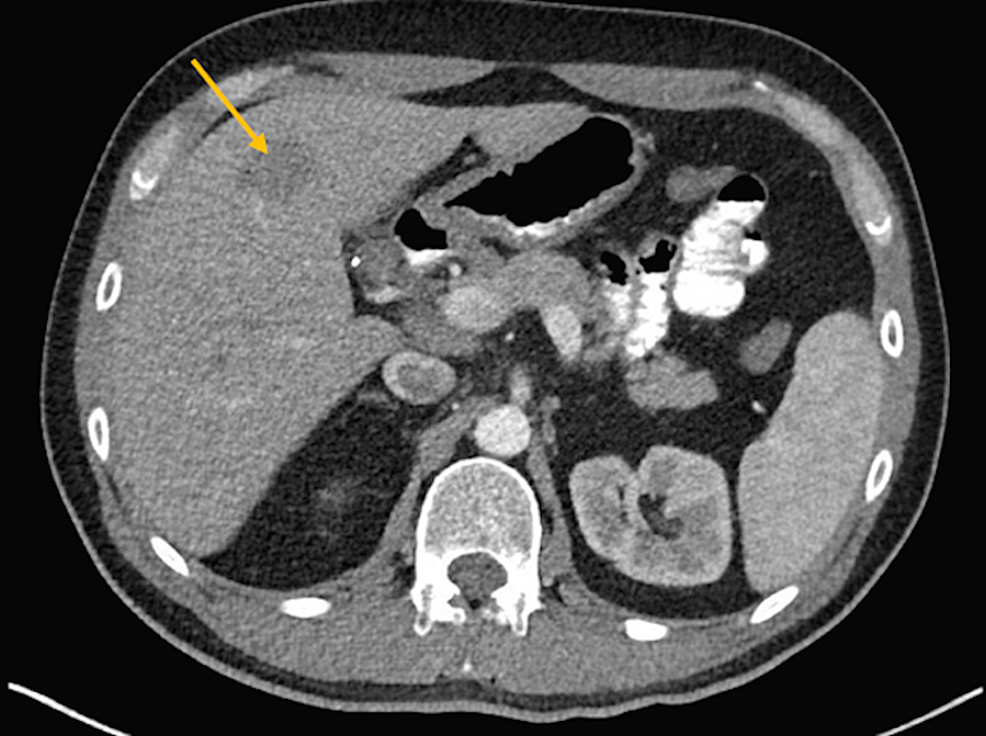

A 46-year-old male with stage IVB nodular sclerosis Hodgkin lymphoma received treatment with six cycles of ABVD (doxorubicin, bleomycin, vinblastine, dacarbazine) and then autologous stem cell transplant. Despite these treatments, he had progression of his disease. The positron emission tomography (PET) showed hypermetabolic activity in the anterior mediastinal mass and left hilar lymph node. He underwent radiation to the mediastinum. A subsequent computed tomography (CT) scan of the chest and liver showed a progression of the anterior mediastinal mass measuring 3.7 x 2.2 cm and a new mass in the left lobe of the liver measuring 2.9 x 2.8 cm (Figures 1-2).